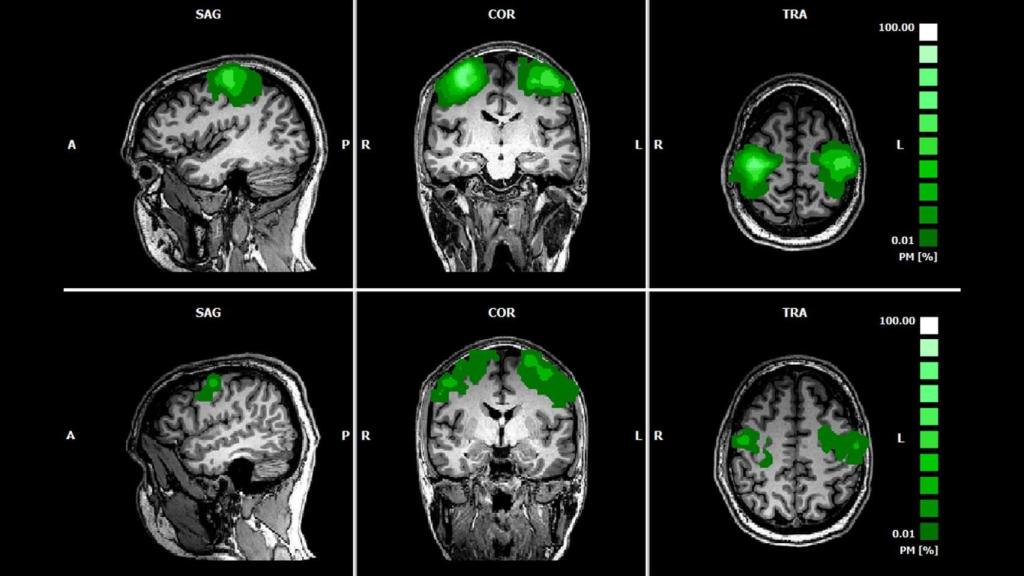

Imágenes de un escáner cerebral usando espectroscopia funcional de infrarrojo cercano

Imágenes de un escáner cerebral usando espectroscopia funcional de infrarrojo cercano Nature Omicrono

La novedad que plantea Connectome Health es el desarrollo de un dispositivo portátil con forma de casco especialmente diseñado para aprovechar la información que puede aportar la espectroscopia funcional de infrarrojo cercano (fNIRS, por sus siglas en inglés), una técnica de neuroimagen que permite estudiar la actividad cerebral de forma no invasiva.

Los sistemas que usan fNIRS se encargan de monitorizar estos cambios en la oxigenación de la sangre para mapear qué partes del cerebro están trabajando.